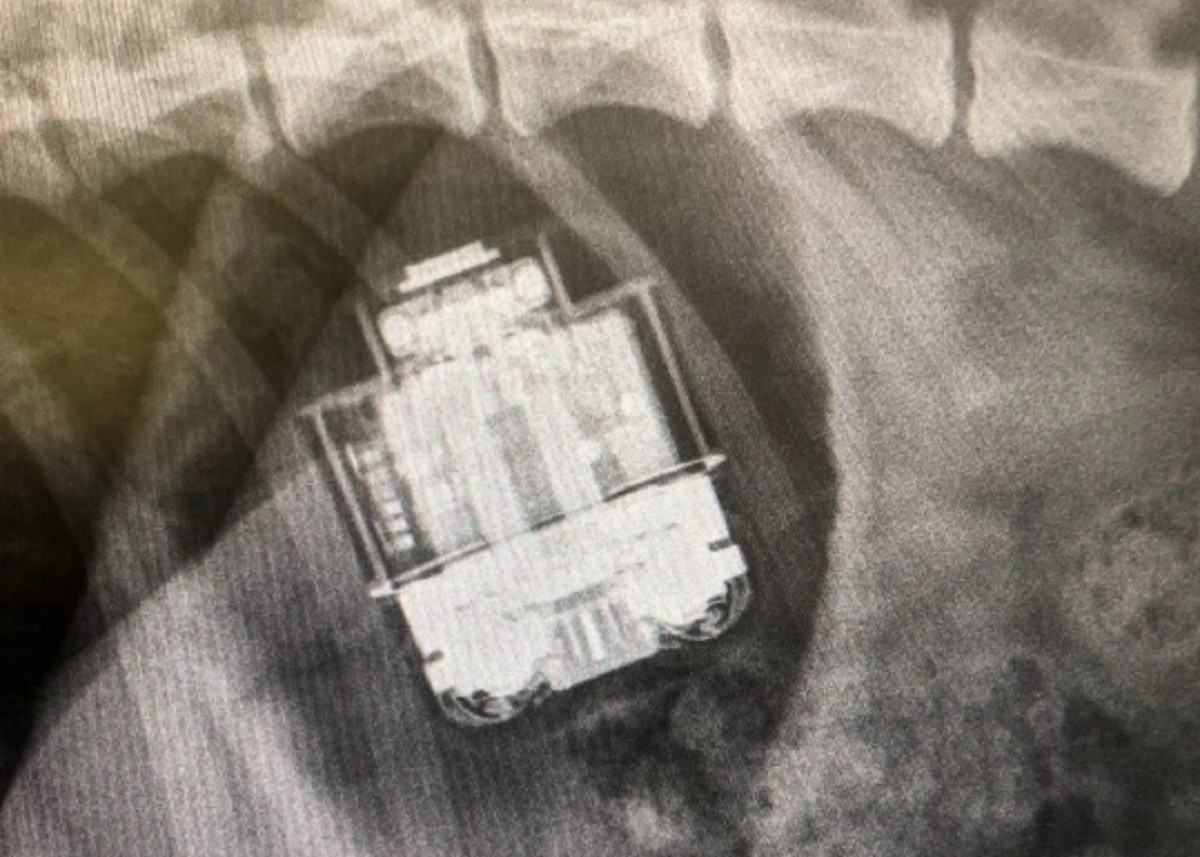

कुत्ते ने निगला एयरपॉड्स, पेट के अंदर भी नहीं हुआ खराब, सर्जरी के बाद निकाला

पालतू कुत्तों की अजीबोगरीब हरकतें अक्सर सामने आती रहती हैं. ऐसा ही एक मामला सामने आया है जहां एक पालतू कुत्ते ने एयरपॉड्स को ही निगल लिया. हालत ये हो गई कि सर्जरी करानी पड़ी हालांकि इससे आश्चर्य जनक बात ये रही कि इसके बाद भी वो एयरपॉड्स चालू था.

दरअसल, यह घटना ब्रिटेन की है, मेट्रो डॉट यूके की एक रिपोर्ट के मुताबिक यहां एक रेचेल हुक नाम एक लड़की को अपने पालतू कुत्ते जिम्मी को अस्पताल ले जाना पड़ा. कारण ये था कि कुत्ते ने एयरपॉड्स निगल लिए थे. जब उस कुत्ते की सर्जरी की गई तो चौंकाने वाला मामला सामने आया.

डॉक्टरों ने उस कुत्ते का चेकअप किया. डर था कि कहीं बैटरी में से निकलने वाला पदार्थ उसके पेट में ना चला जाए, जिससे उसकी जान जा सकती थी. एयरपॉड्स उसके पेट में भी एक्टिव थे और चल रहे थे.

रिपोर्ट के मुताबिक, उनपर कुत्ते के दांत का एक स्क्रैच भी नहीं था. फिलहाल वह कुत्ता ठीक है और घर आ चुका है. धीरे-धीरे वह रिकवर हो रहा है. बताया गया कि कुत्ते को पूरी तरह से ठीक होने में कुछ और दिन लगेंगे.